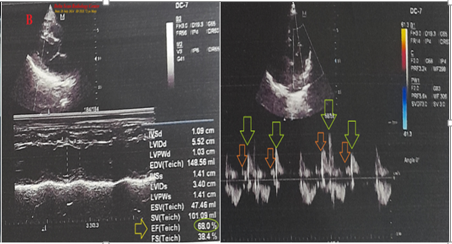

Figure 2b Later echocardiography.

B. Later Echocardiography was done showing a good LV systolic function of an EF of 68% (lime arrow and circle) and grade I diastolic dysfunction (light blue and orange arrows).

A 72-year-old married male farmer Egyptian patient was admitted to the intensive care unit (ICU) with angina, dizziness, and headaches, generalized skin rash within one hour after ingestion of a single sildenafil tablet (25mg). Circumoral numbness and extremities paresthesia were associated symptoms. He gave a recent history of mild fever, generalized myalgia, dry cough, and loss of smell within one week ago and after previous contact with a patient with COVID-19 pneumonia. He gave an old history of chronic obstructive pulmonary disease (COPD). Upon general physical examination; generally, the patient appeared thin, and long, had generalized body hives, look sweaty with an irregular pulse rate (VR of 72), blood pressure (BP) of 90/70 mmHg, respiratory rate of 18 bpm, a temperature of 37°C, and pulse oximeter of oxygen (O2) saturation of 95%. There is a barrel chest on chest inspection and generalized sibilant Ronchi were noted on the chest auscultation. Tests for provocative latent tetany were positive. No more relevant clinical data were noted during the clinical examination. The patient was admitted to the ICU with oral sildenafil-inducing angina. The patient urgently was treated in the ICU with high-flow O2 inhalation via O2 inhalation central system (100%, by simple mask, 10L/min), IM adrenaline 0.5 mg of 1:1000 (single dose), IV hydrocortisone vial (200 mg, then 100mg BID), IV chlorpheniramine maleate ampoule (20 mg, then 10mg BID), IV famotidine ampoule (40 mg, then 40mg BID), and IV Ringer solution (500ml, then 500ml BID). Aspirin; 4 oral tablets (75 mg, then OD), clopidogrel; 4 oral tablets (75 mg, then OD), enoxaparin SC (60 mg, BID), and atorvastatin (20 mg, OD) were added. The patient was hourly monitored for vital signs and O2 saturation. The initial ECG was done on the initial ECG on presentation in the ICU showing sinus arrhythmia (of VR: 70) with ST-segment depression in inferior leads, ST-segment elevation in anterioseptal leads, and evidence of physiological left axis deviation (LAD) (Figure 1A). The second ECG tracing was taken within 20 minutes of the above ECG tracing and after ICU admission showing normal sinus rhythm (NSR) with inferiolateral ST-segment depression, anterioseptal ST-segment elevation, and Wavy triple ECG sign (Yasser’s sign) (Figure 1B). The third ECG tracing was taken within a few seconds of the above ECG tracing and after ICU admission showing NSR (of VR 73) with ST-segment depression in aVF, and V4-6 leads and Wavy triple ECG sign (Yasser’s sign) (Figure 1C). The fourth ECG tracing taken within 2.5 hours after the ICU treatment showed sinus arrhythmia (of VR 64) and Wavy double ECG sign (Yasser’s sign; aVF and V5-6) with normalization of the above ST-segment deviations (Figure 1D). The initial complete blood count (CBC); Hb (15.3g/dl), RBCs (6.39*103/mm3), Hematocrit (44.3%), WBCs (9.6*103/mm3); (Neutrophils; 63.9 %, Lymphocytes: 29.0%, Monocytes; 4.3%, Eosinophils; 2.8% and Basophils 0%), Platelets; 159*103/mm3. SGPT was (39 U/L). Serum creatinine was (1.1mg/dl). RBS was (98 mg/dl). CRP was (9.6mg/dl). Ionized calcium was (3.83mg/d). The troponin test was negative. Chest x-ray was done on the day of the ICU admission showing small left hailer ground-glass opacity (Figure 2A). Later echocardiography showed a good LV systolic function of an EF of 61% and grade I diastolic dysfunction (Figure 2B). Sildenafil-inducing Kounis syndrome in the elderly with intertwining sinus arrhythmia, Wavy triple sign, Wavy double sign (Yasser’s signs), and mild COVID infection was the most probable diagnosis. Nearly complete recovery was achieved within 2.5 hours. The patient was discharged within 3 days of the above management after happening of dramatic improvement in both clinical and electrocardiographic ST-segment depressions and elevations. IV Hydrocortisone (100 mg BID), oral chlorpheniramine maleate (8 mg BID) for 3 days, aspirin tablets (75 mg, OD), oral calcium, and vitamin-D preparations (BID) for 30 days were prescribed on discharge with the recommendation for future cardiac and immunological follow-up.